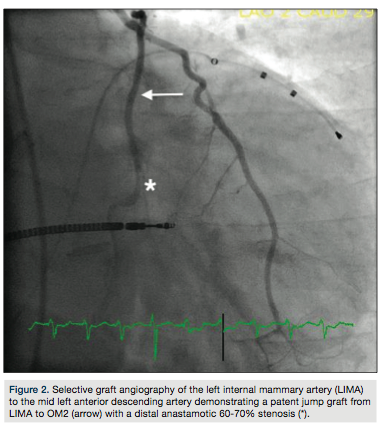

80% stenosis at the second and third obtuse marginal (OM) branch bifurcation, with competitive flow noted in the distal OM2 branch (Figure 1). Selective graft angiography of the left internal mammary artery (LIMA) to the mid left anterior descending artery demonstrated a patent jump graft from LIMA to OM2 with a distal anastamotic 60-70% stenosis (Figure 2). Due to concern for the adequacy of perfusion of the OM2 segment via the native circulation or the jump graft, a strategy to measure the fractional flow reserve (FFR) in the distal OM2 branch was pursued. After maximal hyperemia using intravenous adenosine infusion at 180 mcg/kg/min, maximal FFR was calculated at 0.80 (Figure 3a) with a PressureWire (St. Jude